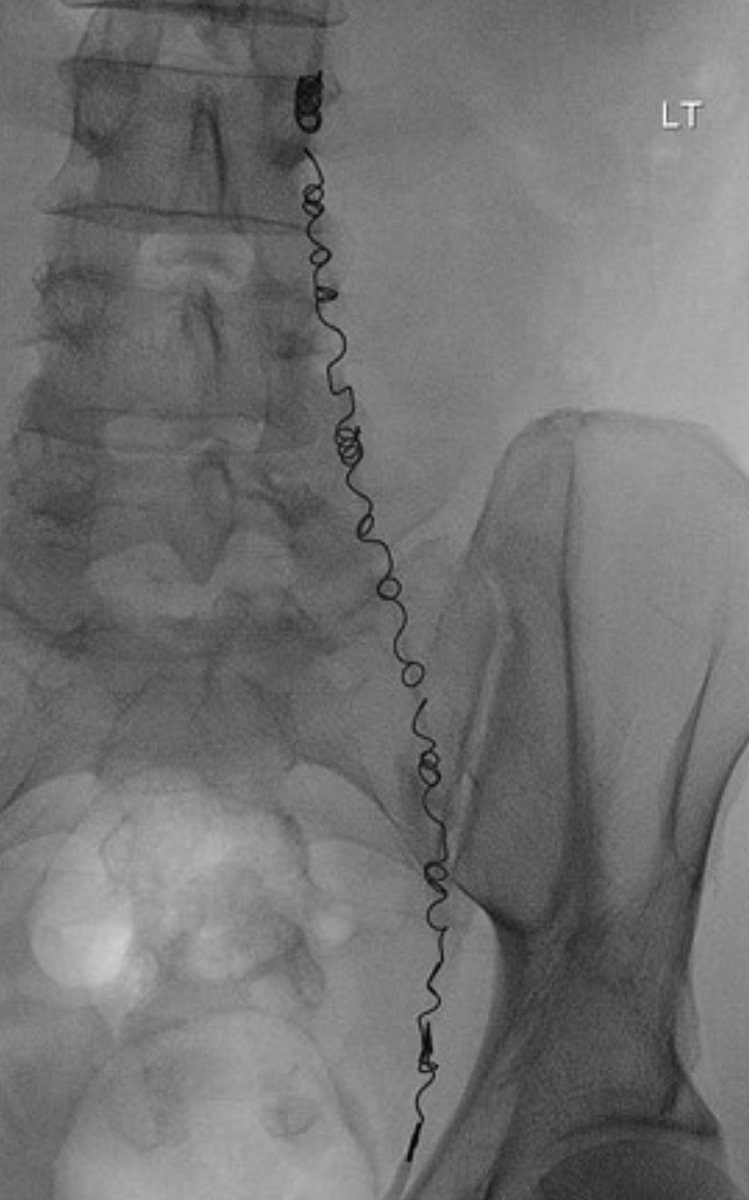

2️⃣الإصلاح بالأشعه التداخليه.

وهو إجراء ممتاز ويعتبر الاول في حالات معينه مثل السمنه المفرطه او لكبار السن حيث تتم عن طريق القسطرة بوضع لولب داخلي واقفال الوريد تحت الاشعه.

قد لا يتناسب لحالات اخرى ..